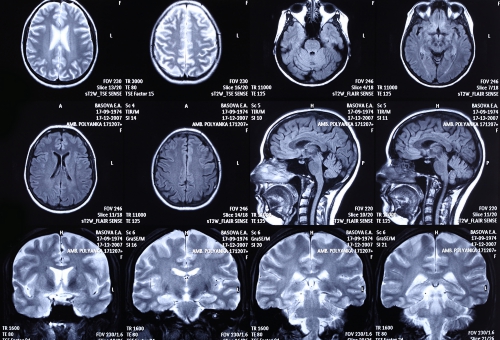

脳は頭蓋骨という骨の中に入っており、最も保護された器官といえます。

脳の図解 Ⅱで、脳は頭蓋骨の中で脳脊髄液に浮かんでいると説明しました、その

脳脊髄液についてもう少し説明します。

脳の皮質(中枢神経)は3枚の髄膜に覆われています。

最も外側が、硬膜(頭蓋骨内側の丈夫な膜)

間に、クモ膜、クモ膜下腔(蜘蛛の巣のように見える)

最も内側が、軟膜(脳の表面に付着している)です。

ここで重要なのが、クモ膜下腔(くもまくかこう)です。

クモ膜下出血とかよく耳にされると思いますが、クモ膜と軟膜の間に存在するスペースには、多数の太い血管と脳脊髄液を含んでいます。ここの血管が何らかの原因で破裂するとクモ膜下出血といわれます。

もう1つは、脳脊髄液です。この液体が脳を頭蓋骨の中で浮かべています。

脳脊髄液は、くも膜下腔、脳室、脊髄の中心管を満たしています。

脳室は、脳内に4つあります。 2つの側脳室、第三脳室、第四脳室です。

脳内の4つの脳室、くも膜下腔、そして脊髄中心管が互いに繋がって1つの貯水槽を作っています。

その貯水槽を満たす脳脊髄液によって脳は保護され、その浮力によって頭蓋骨の中で浮いています。

脳脊髄液を作っている場所は、脳室内面の脈絡叢で持続的に生産され、余分な脳脊髄液はくも膜下から静脈洞(硬膜の中を走っている血液に満たされた大きなスペース)に吸収され頚静脈に注いでいます。